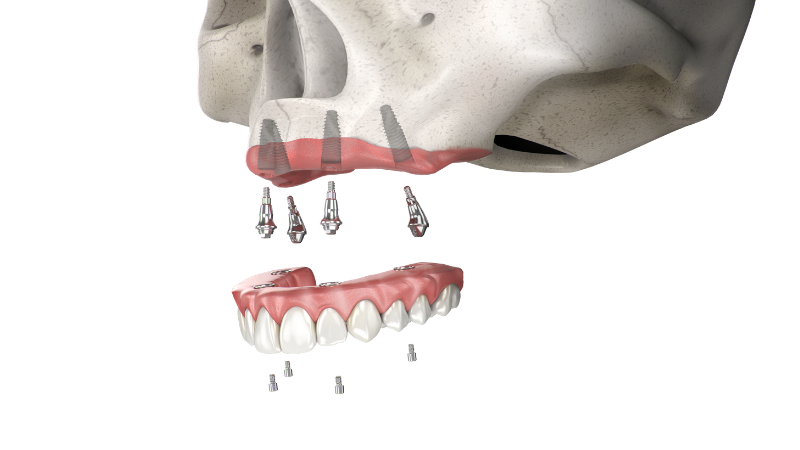

Giải pháp Straumann® ProArch

Straumann® ProArch là giải pháp phục hình toàn hàm cố định tiên tiến, giúp khôi phục chức năng ăn nhai và thẩm mỹ cho bệnh nhân mất răng toàn hàm một cách nhanh chóng và hiệu quả. Dựa trên nền tảng khoa học vững chắc cùng hệ thống implant Straumann® (BLT, BLX) và workflow kỹ thuật số đồng bộ, ProArch cho phép thực hiện quy trình điều trị tức thì với độ ổn định cao và khả năng tiên đoán vượt trội. Giải pháp được thiết kế linh hoạt, tối ưu hóa phân bố lực và hạn chế xâm lấn, mang lại trải nghiệm điều trị an toàn, rút ngắn thời gian hồi phục và nâng cao chất lượng cuộc sống cho bệnh nhân.